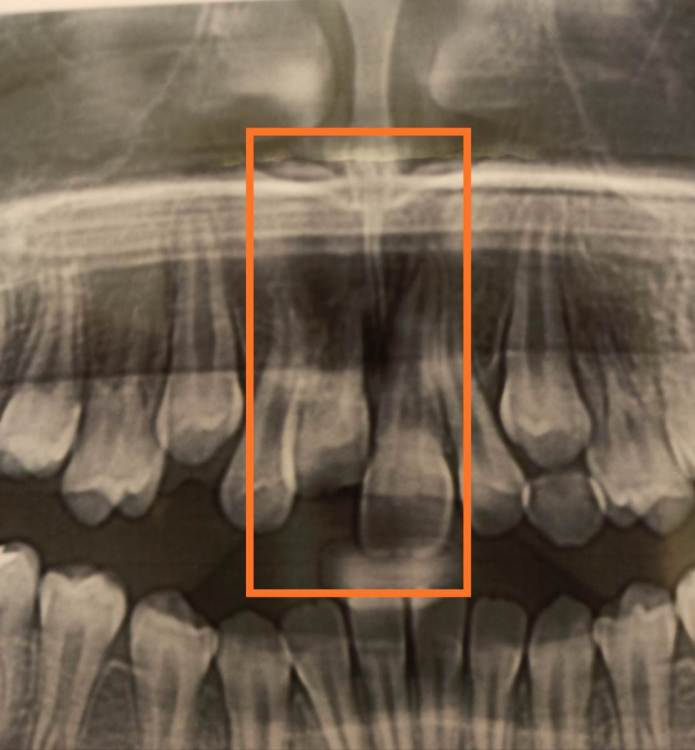

Pole4ka Опубликовано 4 июля, 2021 Поделиться Опубликовано 4 июля, 2021 Добрый день уважаемые специалисты. Три года назад у сына произошла травма, в возрасте 8 лет. Был выбит передний зуб, сломан альвеолярный участок кости. В нашем населённом пункте не было ни одного специалиста, который мог бы помочь в этой ситуации. Через три часа после травмы, были направлены в челюстно-лицевую хирургии в другом городе. Выбитый зуб находился в физрастворе. В итоге, была сделана операция, реплантирован зуб (верхушка зуба на тот момент была не сформирована), добавили костную ткань в месте перелома альвеолярной кости,наложили швы, поставили шины и вывели зуб из прикуса. В течение месяца наблюдались каждый день. Соблюдали все рекомендации по питанию и санации полости. В итоге, зуб прижился. Зуб не депульпировали! На сейчас он ничем не отличается от соседних, единственное, ушел вверх. Через год после травмы поставили расширительные пластины. Т. к. плюс ко всему у нас открытый прикус. Два года пластин. На сейчас ждем полной смены зубов и установки брекетов. Вопрос следующего характера, что можно сказать о текущем состоянии реплантированного зуба и какие шансы его дальнейшего пребывания в полости рта? Есть ли резорбция и другие какие-то минусы? Повторюсь - зуб был не сформирован (верхушка открыта и доктор дал шанс на ревитализацию пульпы). Всем спасибо! Так было ровно год назад Ссылка на комментарий

wladdX Опубликовано 4 июля, 2021 Поделиться Опубликовано 4 июля, 2021 Насколько могу судить по приложенным скринам, резорбция корня всё же есть. Судя по Вашему рассказу, проведённая коллегами работа была верной, результат весьма неплохой. Рассчитывать на длительное пребывание зуба 11 в челюсти не приходится. Когда-то его придётся удалить. 1 1 Ссылка на комментарий

Pole4ka Опубликовано 4 июля, 2021 Автор Поделиться Опубликовано 4 июля, 2021 38 минут назад, wladdX сказал: Насколько могу судить по приложенным скринам, резорбция корня всё же есть. Судя по Вашему рассказу, проведённая коллегами работа была верной, результат весьма неплохой. Рассчитывать на длительное пребывание зуба 11 в челюсти не приходится. Когда-то его придётся удалить. Спасибо большое за Ваше мнение и отклик! Нам бы дотянуть до момента, когда можно будет ставить имплант. Честно говоря, особой разницы между прошлогодним снимком (нижним среди снимков) и панорамным не вижу, поэтому возникла надежда, что резорбция приостановлена. А анкелоза нет? Спасибо! @wladdX Спасибо!!! Ссылка на комментарий

wladdX Опубликовано 5 июля, 2021 Поделиться Опубликовано 5 июля, 2021 Резорбция корня + вертикальное расположение = анкилоз. То что зуб был с несформированной верхушкой корня помогло ему простоять так долго после реплантации в растущей челюстной кости. Конечно, хорошо бы, чтоб зуб смог простоять до имплантации, но на мой взгляд это маловероятно. 1 1 Ссылка на комментарий

Bier Опубликовано 6 июля, 2021 Поделиться Опубликовано 6 июля, 2021 Я вас не порадую: 1. Зуб анкилозирован. 3 часа в физрастворе = нет шансов на реваскуляризацию пульпы и связки. Судя по вашим снимкам однозначно анкилозирование. 2. Что делать теперь и почему: Зуб начал отставать в росте, еще через несколько лет это превратится в нерешаемую эстетическую проблему (вся челюсть будет расти, а зуб и участок челюсти с зубом - нет). Необходимо провести операцию декоронации (спилить коронковую часть зуба глубже уровня костной ткани, удалить то, что осталось от пульпы и дать так зажить. Остатки корня резорбируются сами с замещением на кость. Зато челюсть будет расти вместе с отстальными зубами. восстановить зуб временно на пластике (съемной) потом на брекетах. Имплантация желательно не раньше 21 года. Оставлять так нельзя! Ссылка на комментарий